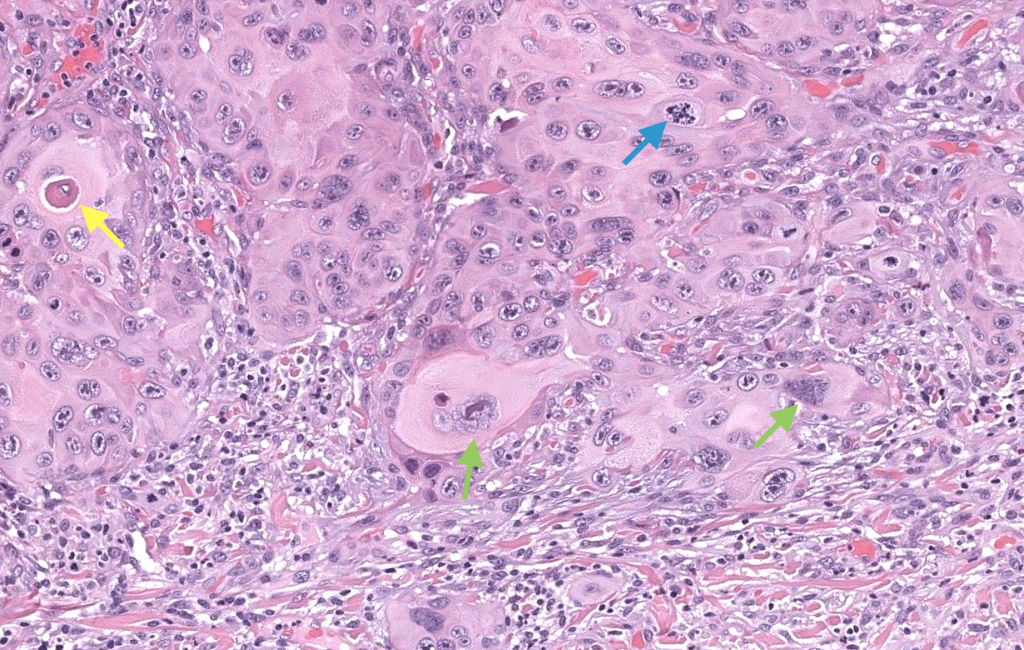

- Neoplasia maligna epitelial originada de queratinocitos epidérmicos, con distinta diferenciación escamosa, potencial de invasión local profunda y metástasis linfática/hematógena. Cassarino 2006, Motaparthi 2017

- Grado de diferenciación (bien/moderado/pobre).

- Grosor tumoral y nivel de invasión (hasta dónde llega).

- Presencia/ausencia de PNI e invasión linfovascular.

- Subtipo histológico (convencional, desmoplásico, fusocelular, verrucoso, etc.).